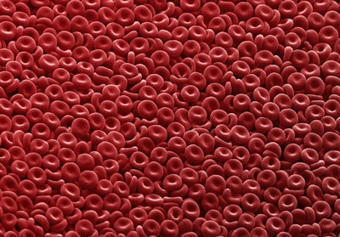

Artificial Blood That Could Work for All Blood Types in Trials

The World Health Organization estimates that more than 118 million blood donations are collected each year—with 40 percent coming from high-income countries, home to 16 percent of the world's population. This means a large portion of the global population has limited access to blood transfusion treatment. Universal artificial blood could reduce preventable deaths in injury, surgery and childbirth—settings where supply mismatches or stockouts cost millions of lives annually in low-income nations alone.

Japanese Scientists Created Universal Artificial Blood

The artificial blood could be a game-changer for blood transfusions as it can safely be administered to all patients regardless of blood type.